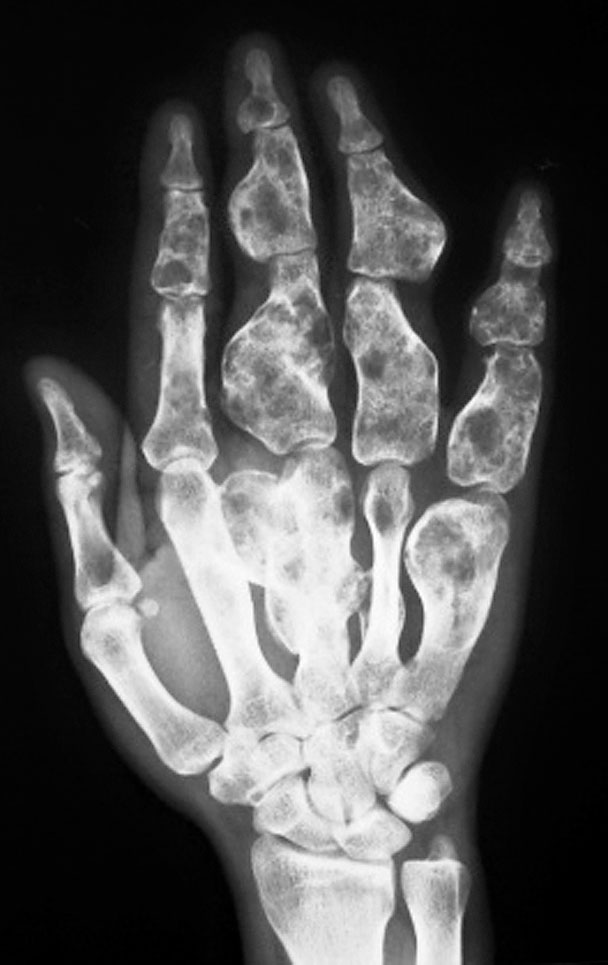

先天性双手指间、掌指关节纤维性(或软骨融合)融合

图1-2-30 指间关节融合X 线片

图1-2-29 指间关节融合